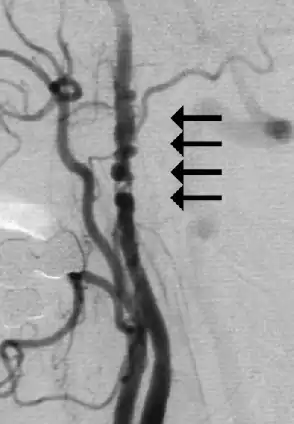

![]() Angiogramă prezentând îngustarea arterelor carotide la o femeie cu AIT[1] | |

Este o urgență medicală.[2] Tratamentul poate include modificări ale stilului de viață, cum ar fi renunțarea la fumat și limitarea consumului de alcool, precum și administrarea de medicamente precum aspirină sau anticoagulante (diluanți ai sângelui).[5] Alte măsuri includ gestionarea tensiunii arteriale, administrarea de statine și controlul zahărului din sânge.[2] La persoanele care prezintă îngustarea arterelor carotide, poate fi indicată o endarterectomie carotidiană.[2] Aproximativ o treime dintre persoanele care au suferit un AIT prezintă un accident vascular cerebral în viitor.[5]